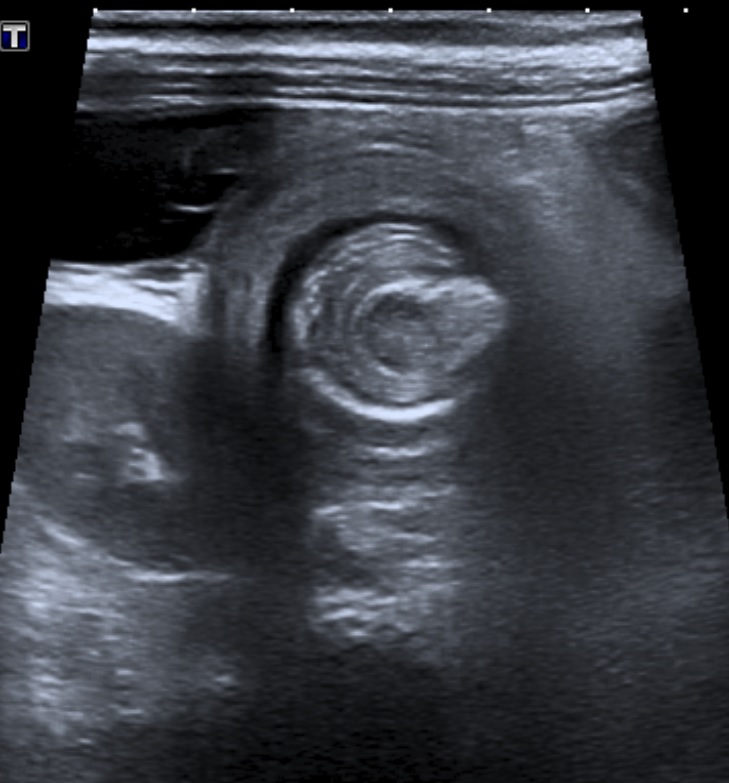

Ecografía abdominal que muestra el signo del donut, compatible con una invaginación a nivel ileocecal.

Se solicita una ecografía abdominal urgente en la que se constata invaginación ileocecal, así como una radiografía en decúbito lateral izquierdo de abdomen que muestra niveles hidroaéreos intestinales en relación con íleo reflejo/oclusión intestinal.